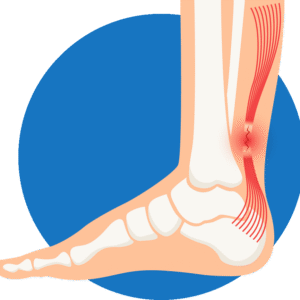

Achilles Tendon Injury (sports injuries)